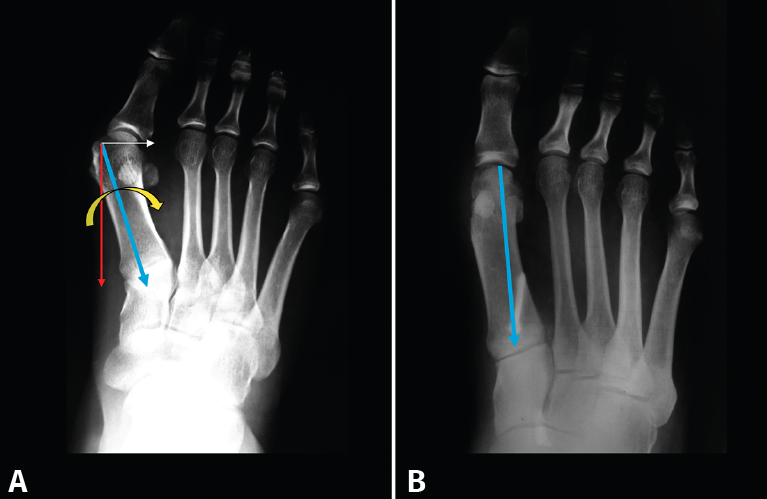

Otro aspecto que ha sido objeto de debate en la literatura es el de la forma y la orientación de la 1.ª ATMT: son muy difíciles de valorar porque se ha visto que varían en función del ángulo de incidencia de la proyección radiológica al tomar la radiografía dorsoplantar. Nuestro grupo(4) hace años realizó un estudio radiológico de forma uniforme sobre 80 pies: todas las radiografías se tomaron en bipedestación y con el mismo ángulo de incidencia del rayo. Los resultados que obtuvimos están representados en la Figura 3A. Se ha postulado (Figura 3B) que la forma curvilínea favorece la aducción y el metatarso varo en el hallux valgus pero, a su vez, favorece la corrección de la deformidad. La forma rectilínea comportaría una articulación más rígida en el plano horizontal(5). De todas maneras otros autores no encuentran relación directa entre la forma de la articulación y la severidad del hallux valgus(6).

Figura 3. A: Distintas formas de primera articulación tarsometatarsiana; B: la forma curva favorece la aducción.